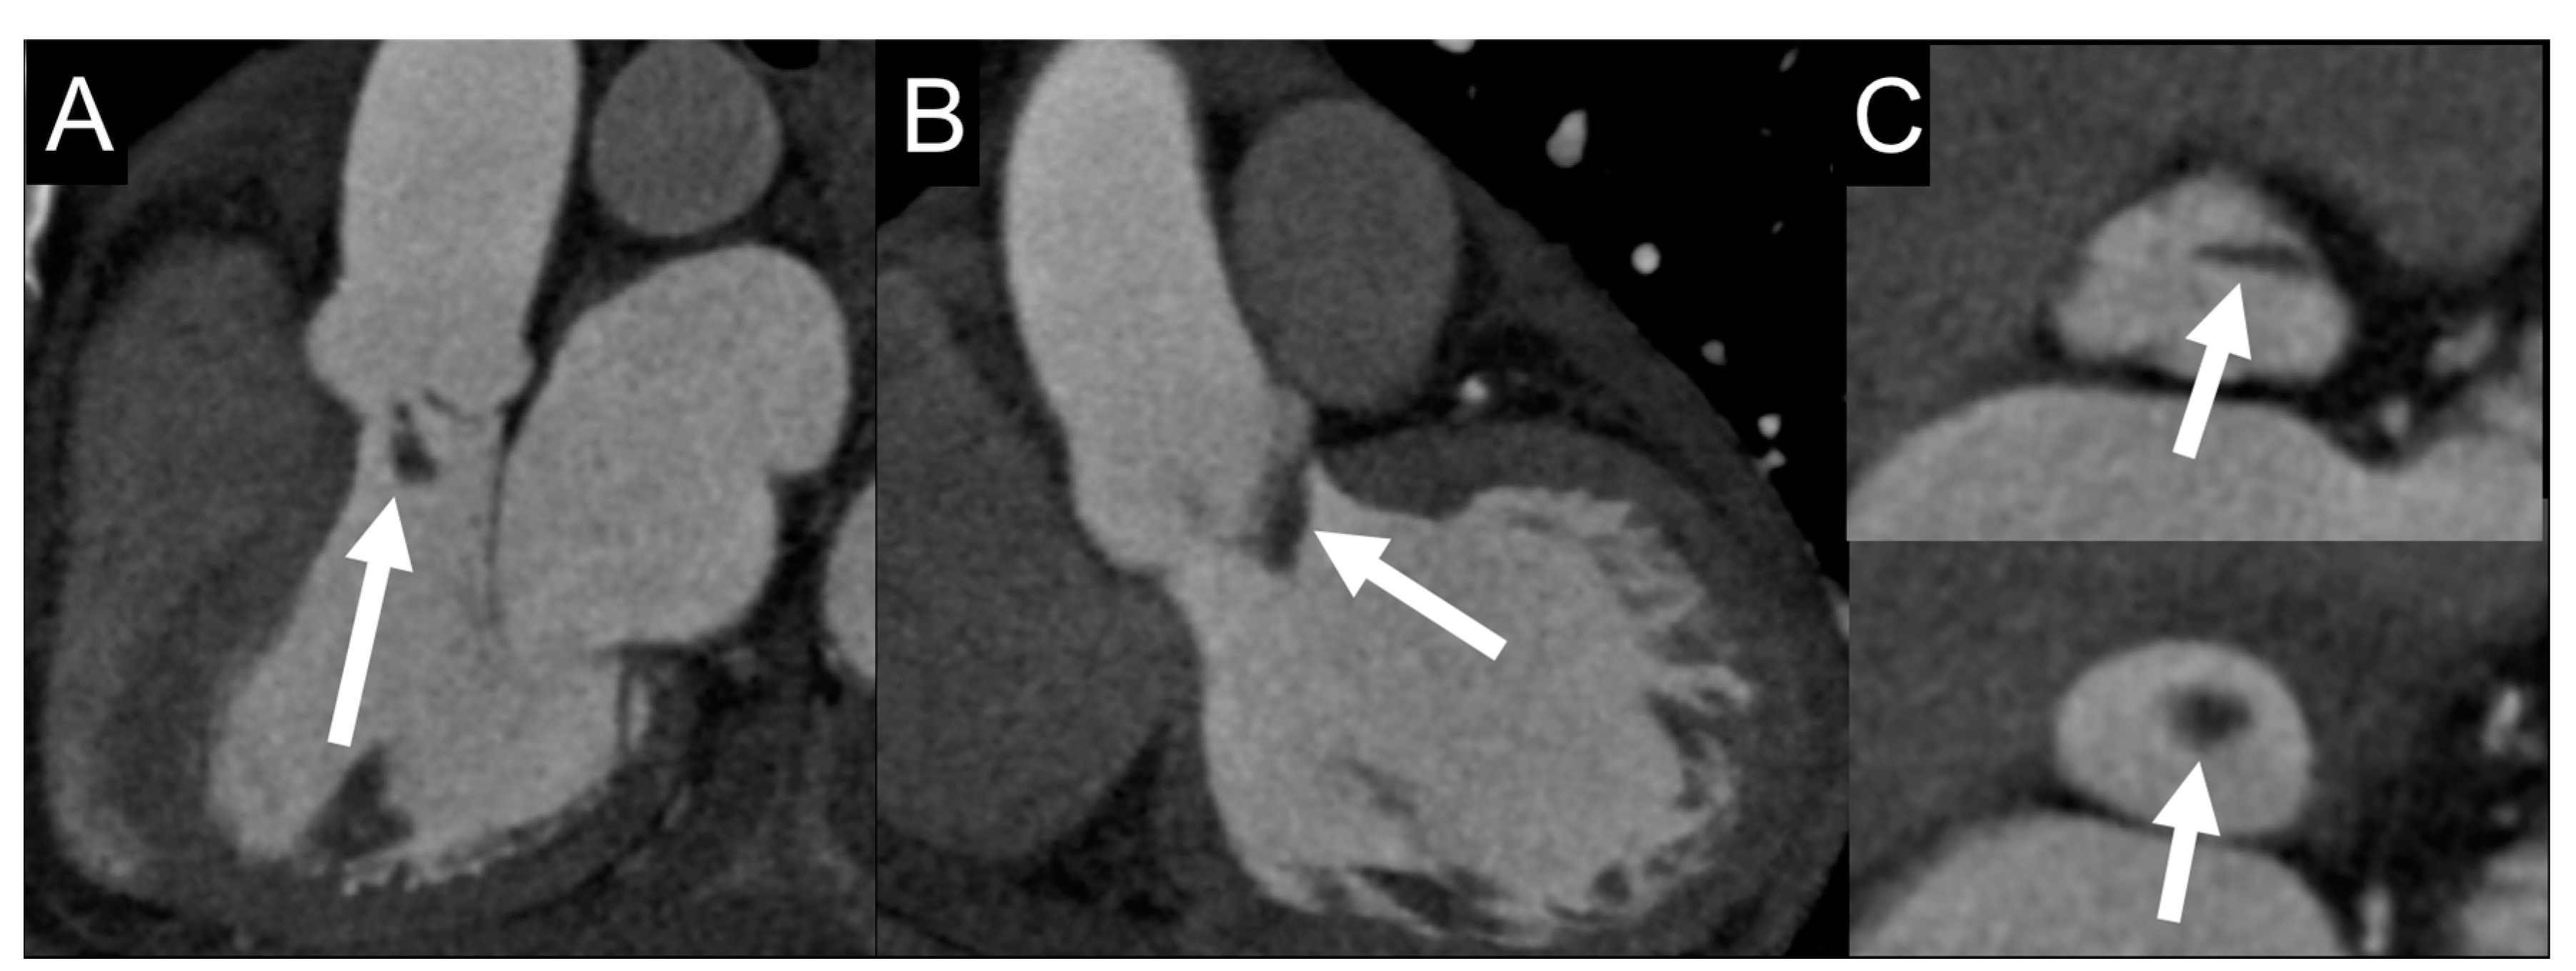

4.3. Role of CCTA in Diagnosing IE and Local Complications

6.3. Role of CCTA in Diagnosing PVE and Local Complication

| Left-sided IE | Good visualization of mitral and aortic valve. Valvular dysfuction assessment. Identification of complication (i.e., valvular regurgitation). | Difficult differential diagnosis in presence of marantic vegetations or high calcification. | Detection of vegetations and valve perforation. Assessment of perivalvular extent of disease (abscesses, pseudoaneursysm, fistula). | Inferior to TTE/TOE in detecting small vegetations (<2 mm). | Prognostic assessment: simultaneous detection of embolism, metastatic lesions and portal of entry. | Limited sensitivity for small vegetations. | Evaluation of distant emboli and portal of entry. | Limited role because of low sensitivity for small vegetations. | Capability to assess vegetations (inferior to TTE/TOE). Capability to assess local complications. Independent by acoustic window. May detect concomitant myocardial inflammation. | Not included in current guidelines for IE diagnosis. |

| PVE | Routinely used for follow up; it allows sequential assessment of prosthesis function. TOE is often required to correctly assess the prosthesis. | Limited by prosthetic material artifacts (i.e., acoustic shadow). Early complication (i.e., abscess) can be difficult to identify. | Identification of complications (paravalvular leakage, abscesses, pseudoaneurysm, dehiscence, and extension to adjacent structures). Capability to visualize large vegetations (>10 mm). | Low image quality for beam hardening artifacts. Limited in assessing small vegetations (<4 mm). | High diagnostic accuracy. Good assessment of perivalvular/periprosthetic complications. Reduction of rate of misdiagnosed PVE. Role in prediction of MACEs. Prognostic significance. | Host reaction may reduce specificity (risk of false-positive studies until 3 months after surgery). | High specificity for infection. Reduction of rate of misdiagnosed PVE. Differential diagnosis between septic and sterile vegetations. | Limited sensitivity for small lesions. | Image quality severely hampered by susceptibility artifacts (especially from mechanical prostheses). | |